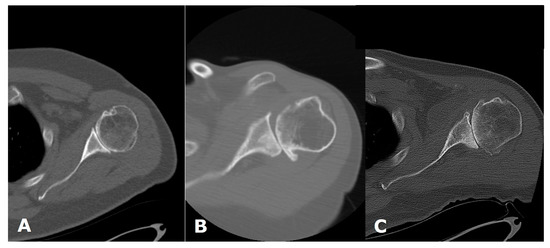

3. Preoperative Imaging

2. Clinical